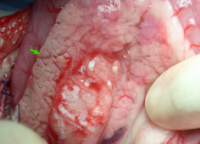

Biopsy